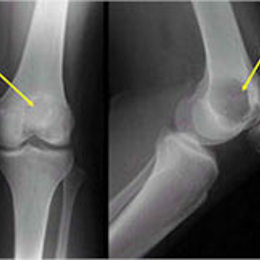

Radiographic imaging is used to help form a diagnosis. These include X-Ray, MRI, CT and Bone Scans

An example of an X-ray is shown.